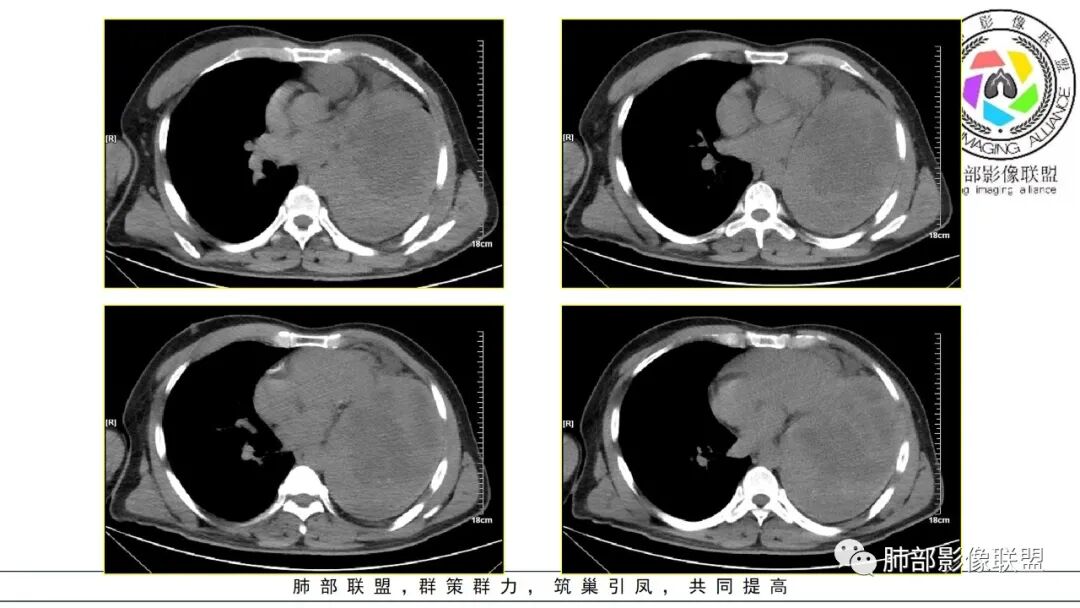

密度:与肿瘤细胞疏松或密集、胶原纤维含量、出血、坏死、囊变及黏液变性等有关。镜下由梭形细胞组成、细胞间由胶原纤维沉积,CT平扫肿瘤实性部分为等、稍低密度,胶原纤维易发生黏液变性或囊变,导致密度不均匀,较少出现钙化。一般肿瘤小,密度多均匀,肿瘤大,多发生坏死、囊变,密度多不均匀。

强化方式:多均匀或不均匀明显强化,增强肿瘤内可见迂曲血管影(蛇纹血管等),肿瘤较大可见“地图样”强化。

恶性倾向:体积较大,多见出血、囊变及坏死;强化多不均匀;呈浸润性生长,与周围组织器官边界不清;出现远处转移等。

3.病灶密度不均,轻度强化,坏死或液化范围甚大,边界可分辨,部分“壁”可见钙化。

4.病灶紧贴胸壁,胸壁未见栽赃侵入。